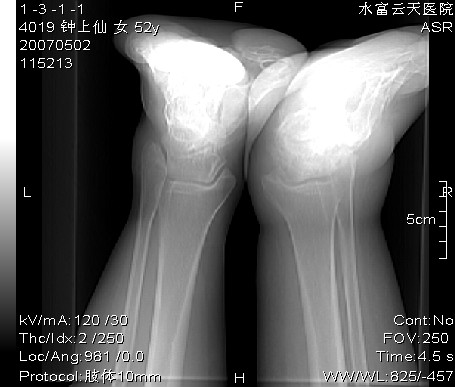

女,52y,自述20多年前外伤骨折,后恢复至今,中间未有不适。两周前发现右足、踝部疼痛,逐渐肿胀,视诊:右足广泛肿胀,发红,皮温稍高,触痛明显。另双侧膝关节疼痛,未见肿胀,未行影像检查。

还有几张图: